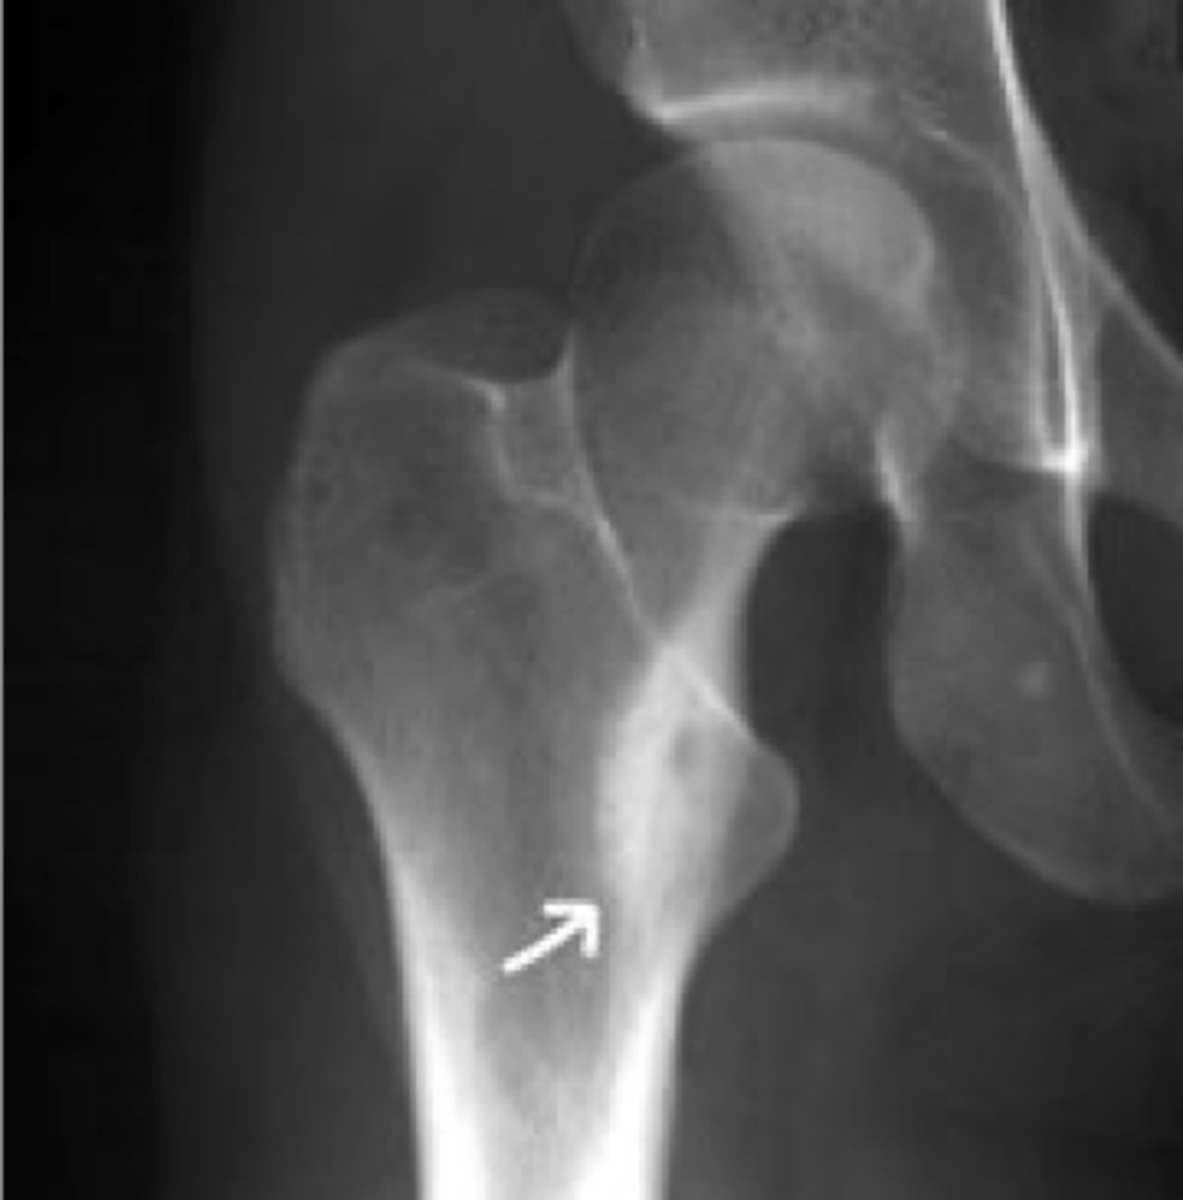

<p>State the radiographic features of simple bone cyst</p>

63

New cards

Pathologic fracture

ID radiographic feature of simple bone cyst indicated by the top arrow

<p>ID radiographic feature of simple bone cyst indicated by the top arrow</p>

64

Fallen fragment sign

ID radiographic feature of simple bone cyst indicated by the bottom arrow

<p>ID radiographic feature of simple bone cyst indicated by the bottom arrow</p>

65

Fallen fragment sign (10%)

- Cortex broke off

- Pathognomonic

<p>- Cortex broke off</p><p>- Pathognomonic</p>